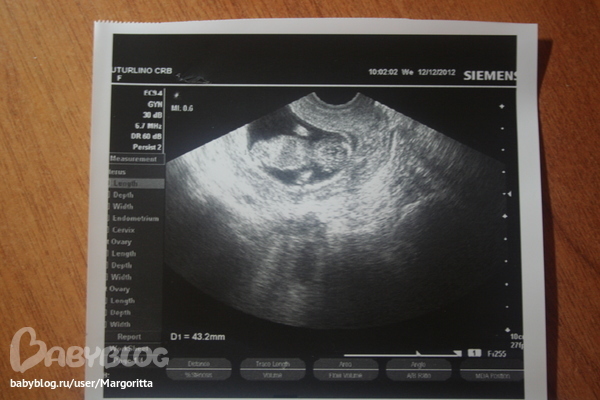

12.12.2012 года ходили мы смотреть на нашего малыша)))

так здорово))) услышали наше сердечко 164 удара в минуту. срок 11 нед.3 дня (на 12.12.2012 по месячным было 11 нед и 4 дня) рост 43 мм.

показали ручки, ножки, пальчики, "бабочку" мозга. в общем сказали что все у нашего счастья хорошо, что он наверное спит, потому что махнул ручкой только один раз.